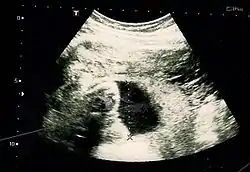

Image by Dahab AA, Aburass R, Shawkat W, Babgi R, Essa O, Mujallid RH

Suspicion of an abdominal pregnancy is raised when the baby‘s parts can be easily felt, or the lie is abnormal, the cervix is displaced, or there is failed induction of labor.[4] X-rays can be used to aid diagnosis.[9]